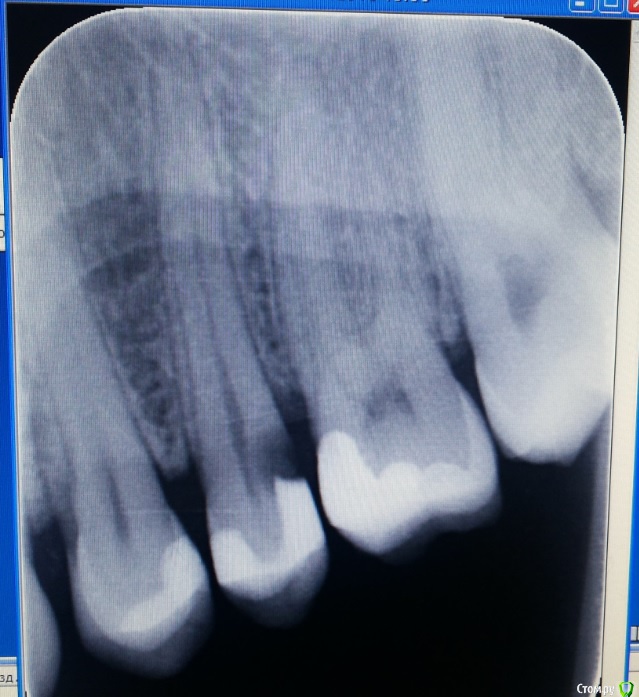

Verasss Опубликовано 11 сентября, 2016 Поделиться Опубликовано 11 сентября, 2016 Здравствуйте! Посоветуйте, пожалуйста! Имеется 25-й зуб, запломбированный месяц назад горячей гуттаперчей, инъекционный метод вертикальная конденсация. Постоянная боль уже месяц после пломбировки, чувство внутреннего отека, одонтогенный гайморит (по кт и симптомам) как следствие. До пломбировки не беспокоил. Единственное, что переходила с каласептом - 17 дней. Зуб депульпировали сразу, поставили каласепт на неделю, я проходила с ним 17 дней. Потом запломбировали 08.08 горячей гуттаперчей, вертикальная конденсация. Постпломбировочные боли в течение недели.Через неделю осталась ноющая боль и ощущения отека где-то внутри в десне. с 08.08 по 22.08 принимала обезболивающие (кетанов+найз), так как спать и разговаривать было больно.22.08 несмотря на мои жалобы на ноющую боль, мне сняли временную и поставили постоянную пломбу. Два дня боли не было, потом она возобновилась, отдавала в передние зубы, в ноздрю, куда-то в бровь. Больно было разговаривать. Обезболивающие днём и на ночь.29.08 боль ушла, необходимость пить обезболивающие отпала. Cохранился отёк, ощущение, чтобы зубы или прикус не встали на место, щелкает челюсть слева, при надавливании на зуб он чувствителен, зуб убран из прикуса по максимуму. 05.09. Боль вернулась. Если зуб или десну рядом потревожить начинается ноющая боль, которая сама по себе не прекращается. Болит как бы не сам зуб, а ткани под ним и окружающие его. 07.09 сделала кт, по которому вся гайморова пазуха со стороны зуба заполнена. Вторая чистая. с 08.09 начала принимать антибиотики. Сейчас есть признаки гайморита, немеет ноздря, отек губы (прошел, немного отек щеки), иногда отдает в лоб, голову, передние зубы, но нос чистый без насморка. Перкуссия зуба по-прежнему очень чувствительна, такни вокруг ноют и есть ощущение их мягкости. Вопрос: вскрывать зуб и лечить кальцием или "само пройдёт" на антибиотиках??Параллельное лечение у ЛОРа рекомендовано, само собой. Хотя гноя, как я понимаю у меня пока нет. Прилагаю снимок "до" и "после" (с временной пломбой от 15.08). Есть ещё КТ, могу загрузить папку со всеми фото, программа для просмотра у меня не открывается. Спасибо за содействие! Ссылка на комментарий

dok1 Опубликовано 12 сентября, 2016 Поделиться Опубликовано 12 сентября, 2016 Канал перебрать бы. Не до верхушки пломбирован слегка. Ссылка на комментарий

Ker Опубликовано 15 сентября, 2016 Поделиться Опубликовано 15 сентября, 2016 (изменено) Да простят меня терапевты, мне не нравится ваш зуб... разрушение ниже уровня десны, контактный пункт не создан..Дистально уступ получился, похоже что матрицу недотянули до края зуба, плюс еще стоит посмотреть насчет второго канала. Недопломбировка есть однозначно, хоть и небольшая, канал открывается прямо на рентген апексе. Само не пройдёт. Изменено 15 сентября, 2016 пользователем Ker Ссылка на комментарий